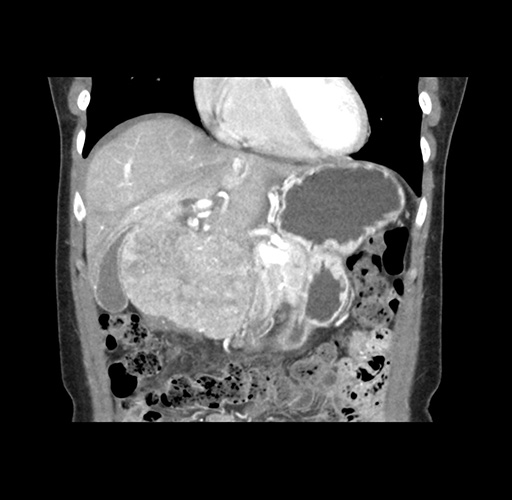

Imaging Analysis

Look through the patient's CT scan to identify any areas of concern for the necessary procedure.

Based on your CT findings, which issue(s) would give reason for "planned slowing down moment(s)" in this case?